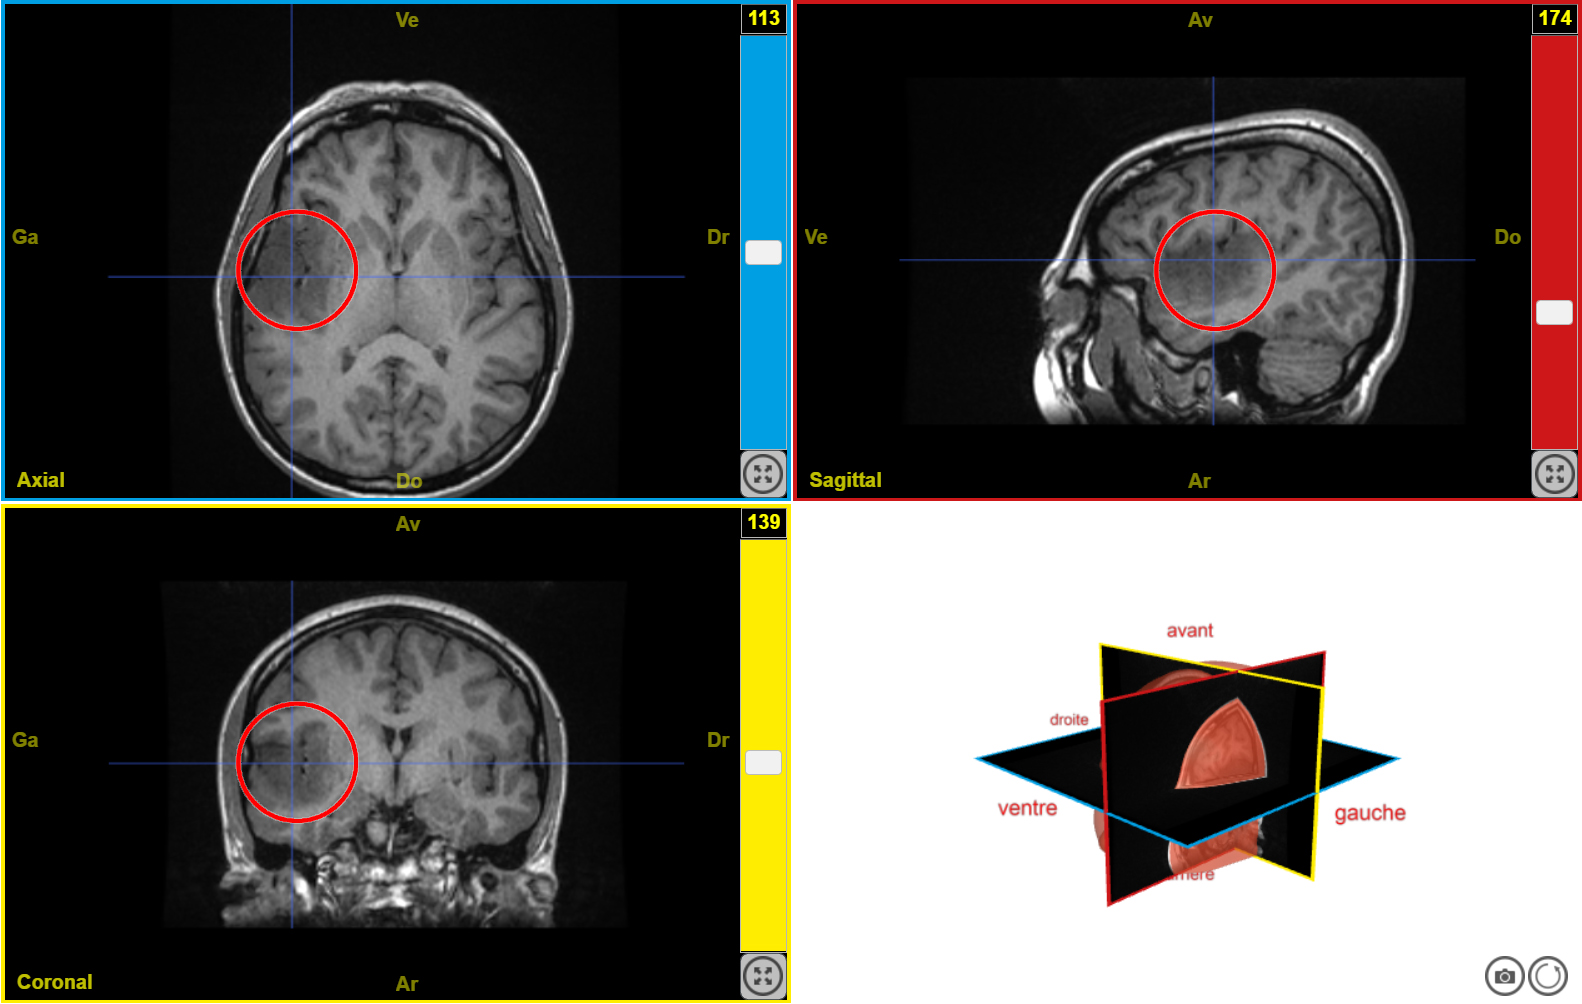

IRM tumeur T1 n2